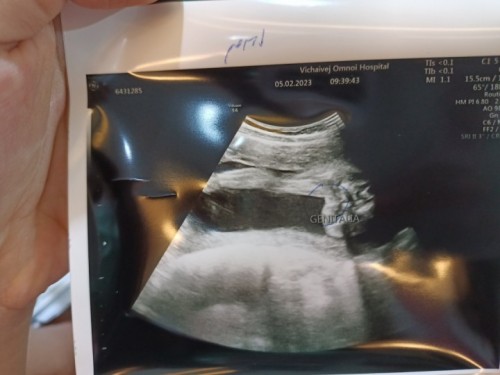

ลูกสาวใช่ไหมค่ะ คุณหมอบอกลูกสาว 80% แม่ๆ ช่วยดูหน่อยจ้า

น่าจะลูกสาวค่ะ